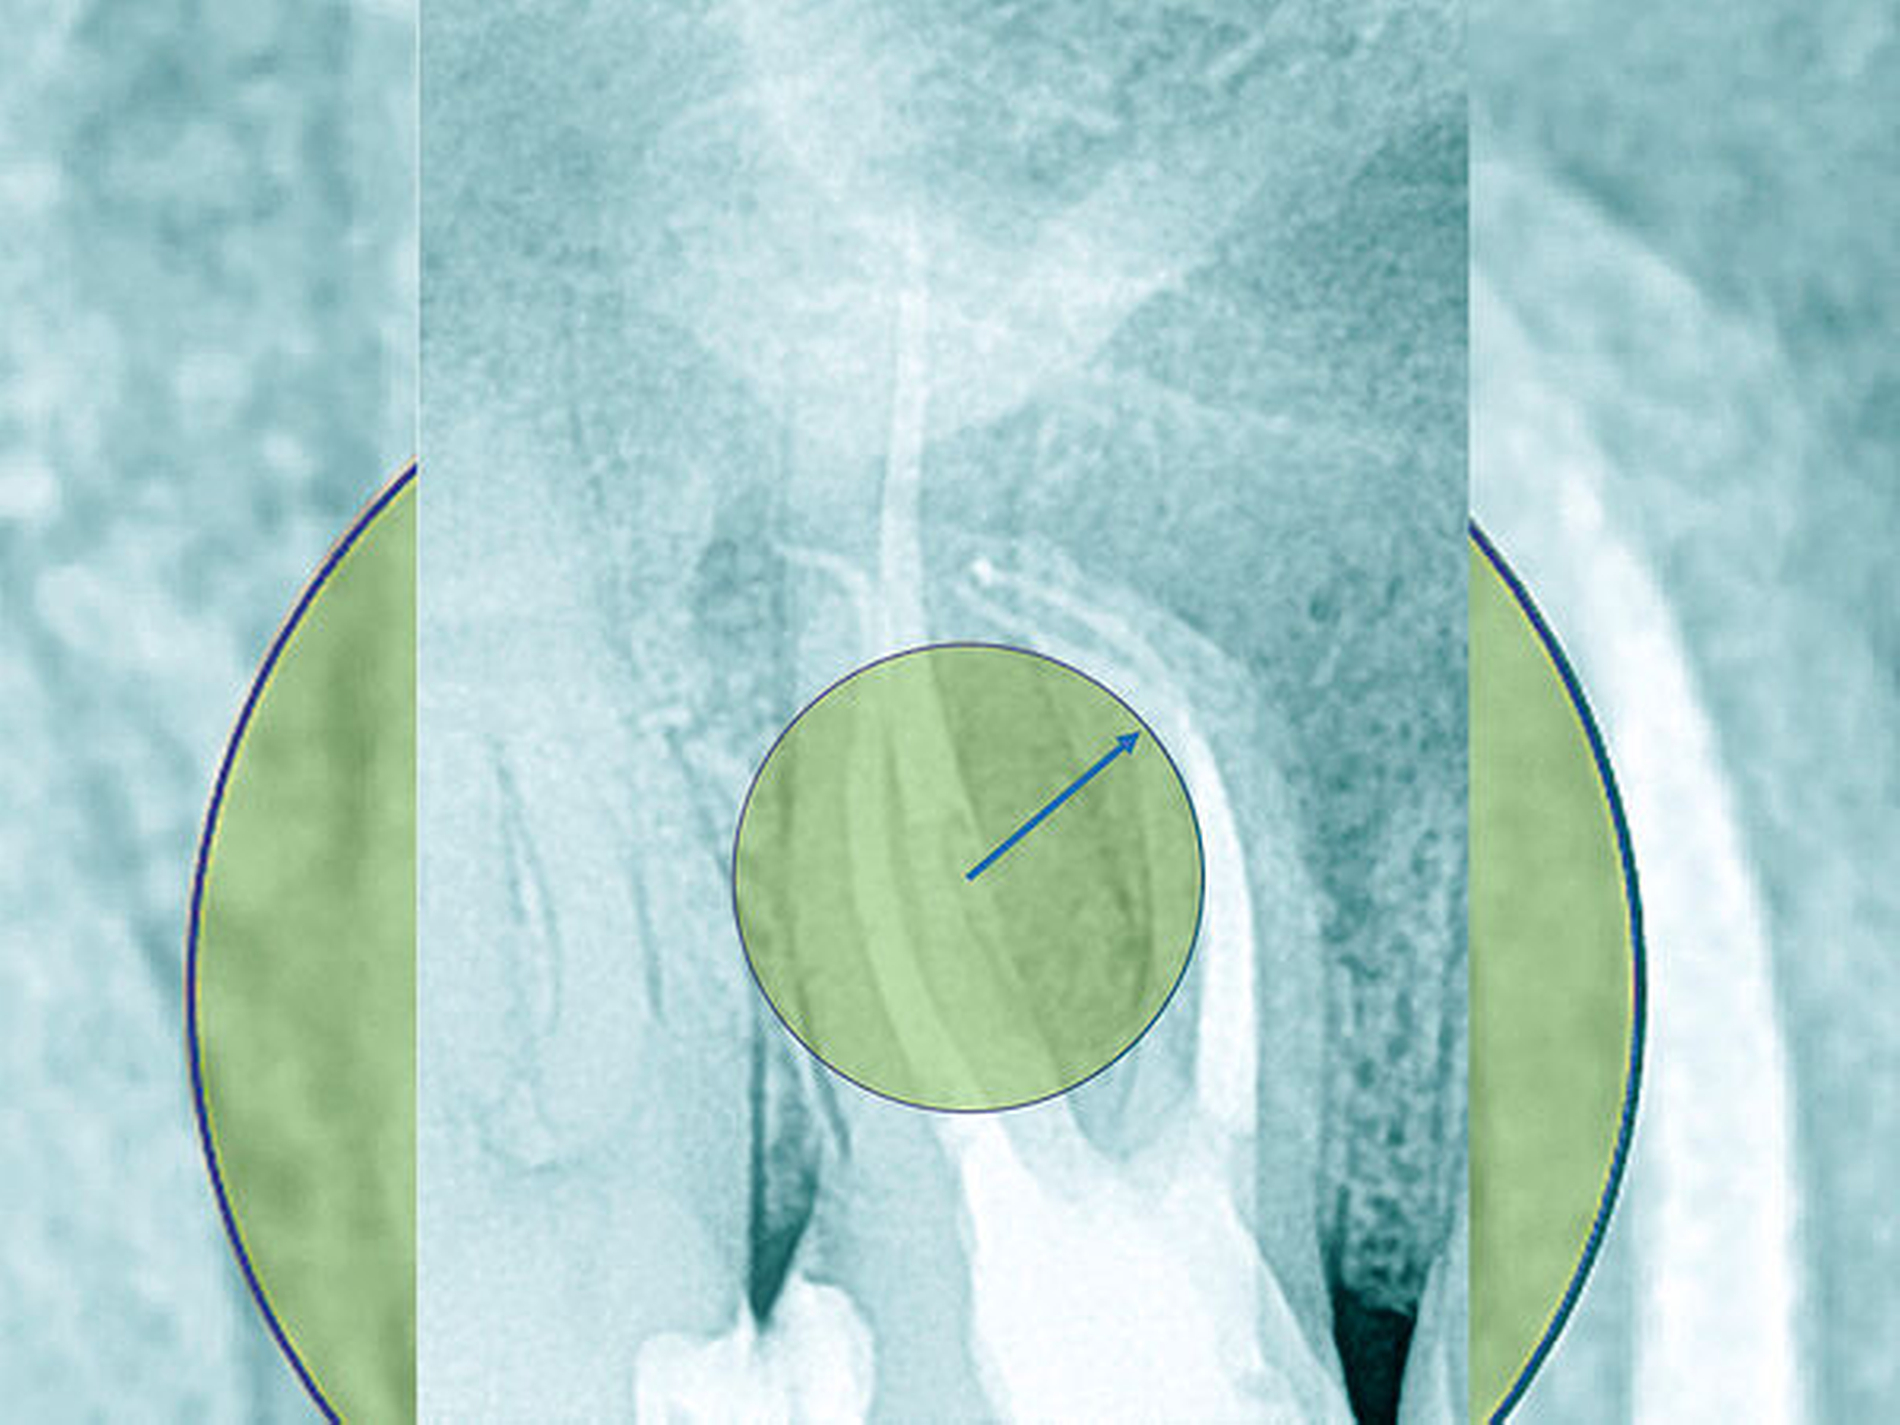

Die Schwierigkeit in der Therapie nimmt zu, wenn die Wurzelkanalkrümmung mehr als 30 Grad beträgt, der Krümmungsradius abnimmt (enge Krümmung) oder Mehrfachkrümmungen vorliegen [Duke et al., 2015; Pedulla et al., 2020]. Typisch für Mehrfachkrümmungen sind vor allem mesiale Wurzelkanäle unterer Molaren (Abbildung 4).

Jede erforderliche endodontische Revision ist eine Summe von mehreren endodontischen Problemstellungen, die die Grenzen einer bisher unter normalen zahnärztlichen Bedingungen möglichen Wurzelkanalbehandlung aufzeigt. Eine Korrektur ist meist nur unter Zuhilfenahme spezieller Hilfsmittel und einer optimalen optischen Vergrößerung möglich (Abbildung 5) [Imura et al., 2007; Naito, 2010].